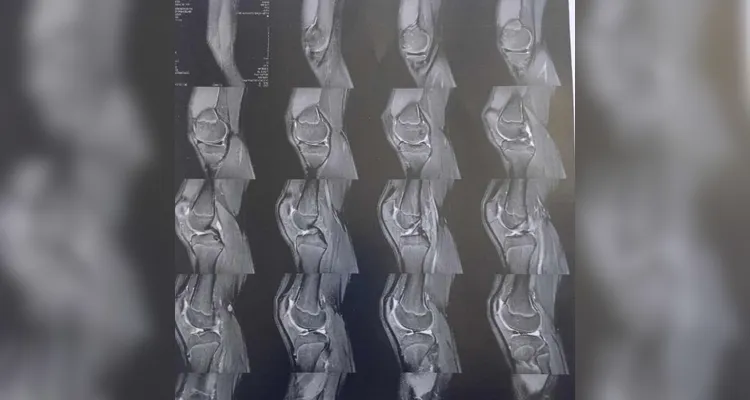

Kaua Rodrigo Santos Gonçalves, de 13 anos, precisa realizar o procedimento com urgência em seu joelho direito após sofrer uma ruptura e deslocamento do menisco por conta de um acidente

A família do jovem Kaua Rodrigo Santos Gonçalves solicita a sua ajuda para a realização de uma cirurgia de caráter urgente que pode salvar a perna do jovem de 13 anos. No dia 14 de outubro, Kaua sofreu uma queda no colégio em que estuda em Ponta Grossa, o que resultou em uma ruptura e deslocamento do menisco em seu joelho direito. Com a lesão, o jovem passou a ter dificuldades de se locomover, necessitando de suporte dos familiares para locomoção diária.

Após a realização de exames, os médicos constataram a necessidade da realização de um procedimento cirúrgico com urgência. Kaua entrou na fila do Sistema Único de Saúde (SUS), mas segue sem previsão da realização da cirurgia. Por conta da demora, a perna de Kaua segue perdendo massa muscular e corre o risco de atrofiar, podendo causar o encurtamento da perna e a perca total da locomoção no membro por conta do seu joelho fraturado.

Confira abaixo a documentação contendo os exames e o custo da cirurgia.